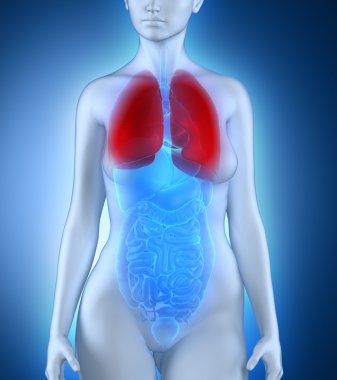

çizim, pulmoner dolaşım

ArkaplankişiİnsanKadınkanİlaçSolunumAvrupa DiliKardiyolojikalpdüzresim çalışmasıAkciğerSistemkemergemiüstünvenanatomiNormalauricletedavülarterAzalanyükselenCavaaortvena cavatorasikaşağıPulmonerventrikül20 30 yıldüz arka planKan damarıSolunum SistemiKan dolaşımıPnömolojiaortik kemerinen aortPulmoner dolaşımtorasik aortyükselen aortaPulmoner arterBenzer İçerikler